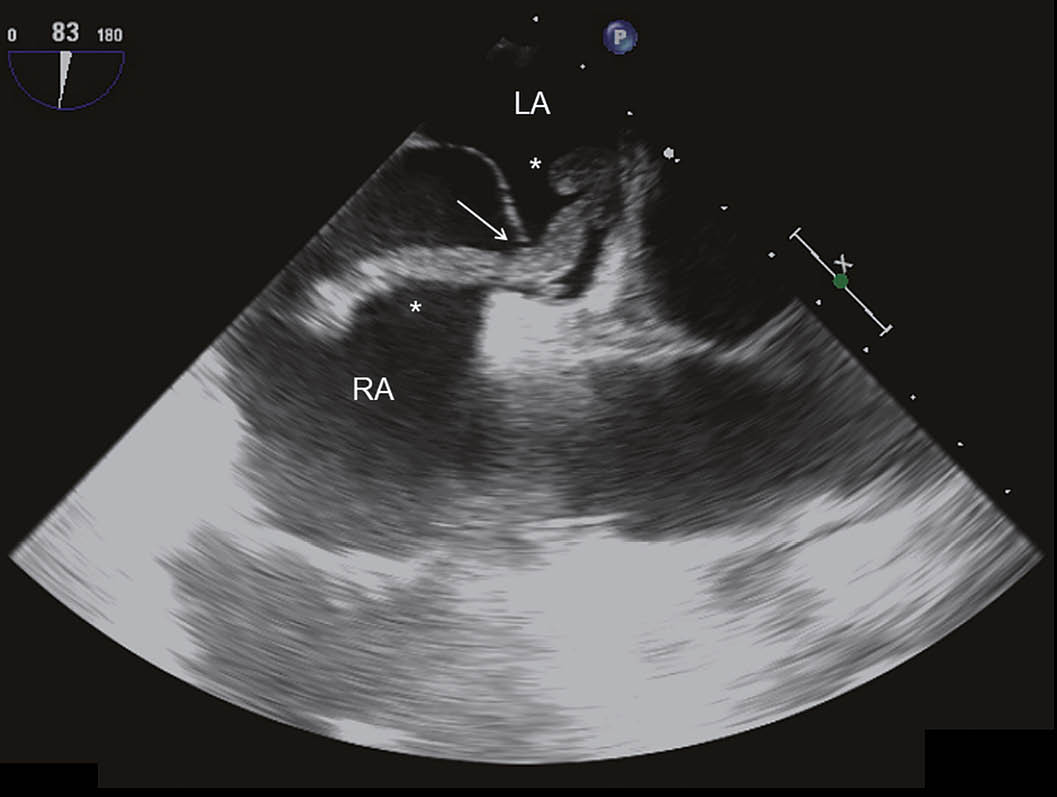

Ein 52-jähriger Patient musste sich wegen eines bronchialen Plattenepithelkarzinoms einer linksseitigen Unterlappenresektion unterziehen. Einige Tage postoperativ klagte der Patient plötzlich über starke Schmerzen im rechten Bein. Ferner bestand eine zunehmende Dyspnoe. Es zeigte sich im ischämischen rechten Bein ein ausgedehnter arterieller Gefässverschluss, welcher durch einen komplexen notfallmässigen Eingriff mit Thrombendarterektomie und Thrombektomie behandelt werden konnte. Die weiteren Abklärungen ergaben den Nachweis von tiefen Beinvenenthrombosen und von ausgedehnten beidseitigen Lungenembolien. Im Labor zeigte sich eine Thrombozytopenie und es wurde die Diagnose einer heparininduzierten Thrombozytopenie Typ II gestellt. Entsprechend wurde die Antikoagulation auf Bivalirudin umgestellt. Im Rahmen der Untersuchungen wurde eine transthorakale Echokardiographie durchgeführt. Hierbei zeigte sich ein dilatierter, exzentrisch hypertropher rechter Ventrikel (Abb. 1) und es fanden sich Zeichen einer ausgeprägten pulmonal-arteriellen Hypertonie (Abb. 2). Im rechten Vorhof zeigte sich ein grosser Thrombus, welcher am interatrialen Septum adhärent zu sein schien (Abb. 3). Ein Teil des Thrombus prolabierte durch die Trikuspidalklappe in den rechten Ventrikel (Abb. 4). Es wurde interdisziplinär entschieden, den grossen ‘Thrombus-in-Transit’ nach Stabilisierung des Patienten operativ zu entfernen. Die intraoperativ durchgeführte transösophageale Echokardiographie liess erkennen, dass der Thrombus nun durch ein persistierendes Foramen ovale (PFO) in den linken Vorhof prolabierte (Abb. 5). Bei der operativen Entfernung zeigte sich, dass der Thrombus in Fäden der Valvula Eustachii verfangen war (Abb. 6), was eine weitere Migration des Thrombus verhinderte. Der Anteil, welcher durch das PFO prolabierte, liess sich ohne Widerstand herausnehmen. Nach Entfernung des Thrombus wurde das Foramen ovale verschlossen. Die Operation verlief erfolgreich. Nach initial protrahiertem Verlauf erholte sich der Patient sehr gut und es zeigte sich eine deutliche Regredienz der pulmonal-arteriellen Hypertonie. Die Antikoagulation mit Bivalirudin wurde in der Folge auf Marcoumar umgestellt; es kam zu keinen weiteren thromboembolischen Komplikationen.

Abb. 5: Intraoperative transösophageale Echokardiographie mit Blick auf die Atria und das interatriale Septum.

Es zeigt sich, dass der Thrombus (*) nun durch ein persistierendes Foramen ovale (Pfeil) in das linke Atrium prolabiert. RA bedeutet rechtes Atrium und LA linkes Atrium.